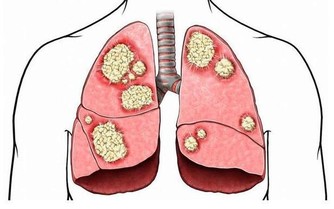

腎臟是人體最重要的代謝器官之一,如果腎臟出現了問題,那麼我們體內的毒素就無法正常代謝,

從而破壞我們機體內環境的穩定,引發很多健康問題。

當我們的腎臟出現問題時,我們的身體會出現一些症狀,

這時,如果大家忽視這些症狀,就有可能早晨腎臟更為嚴重的病變。